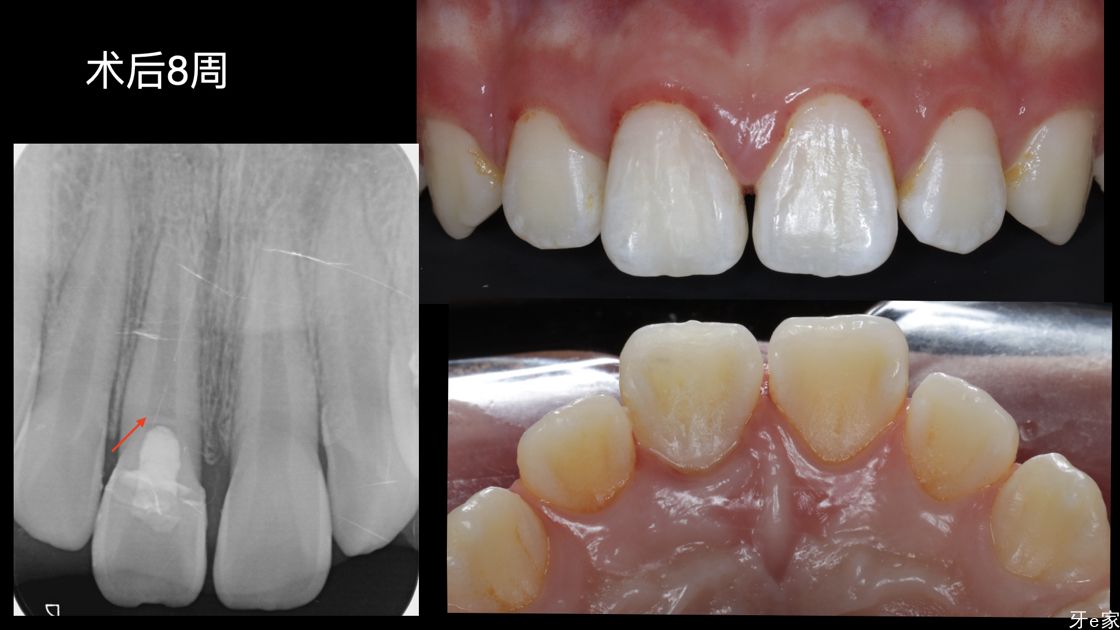

术后总结